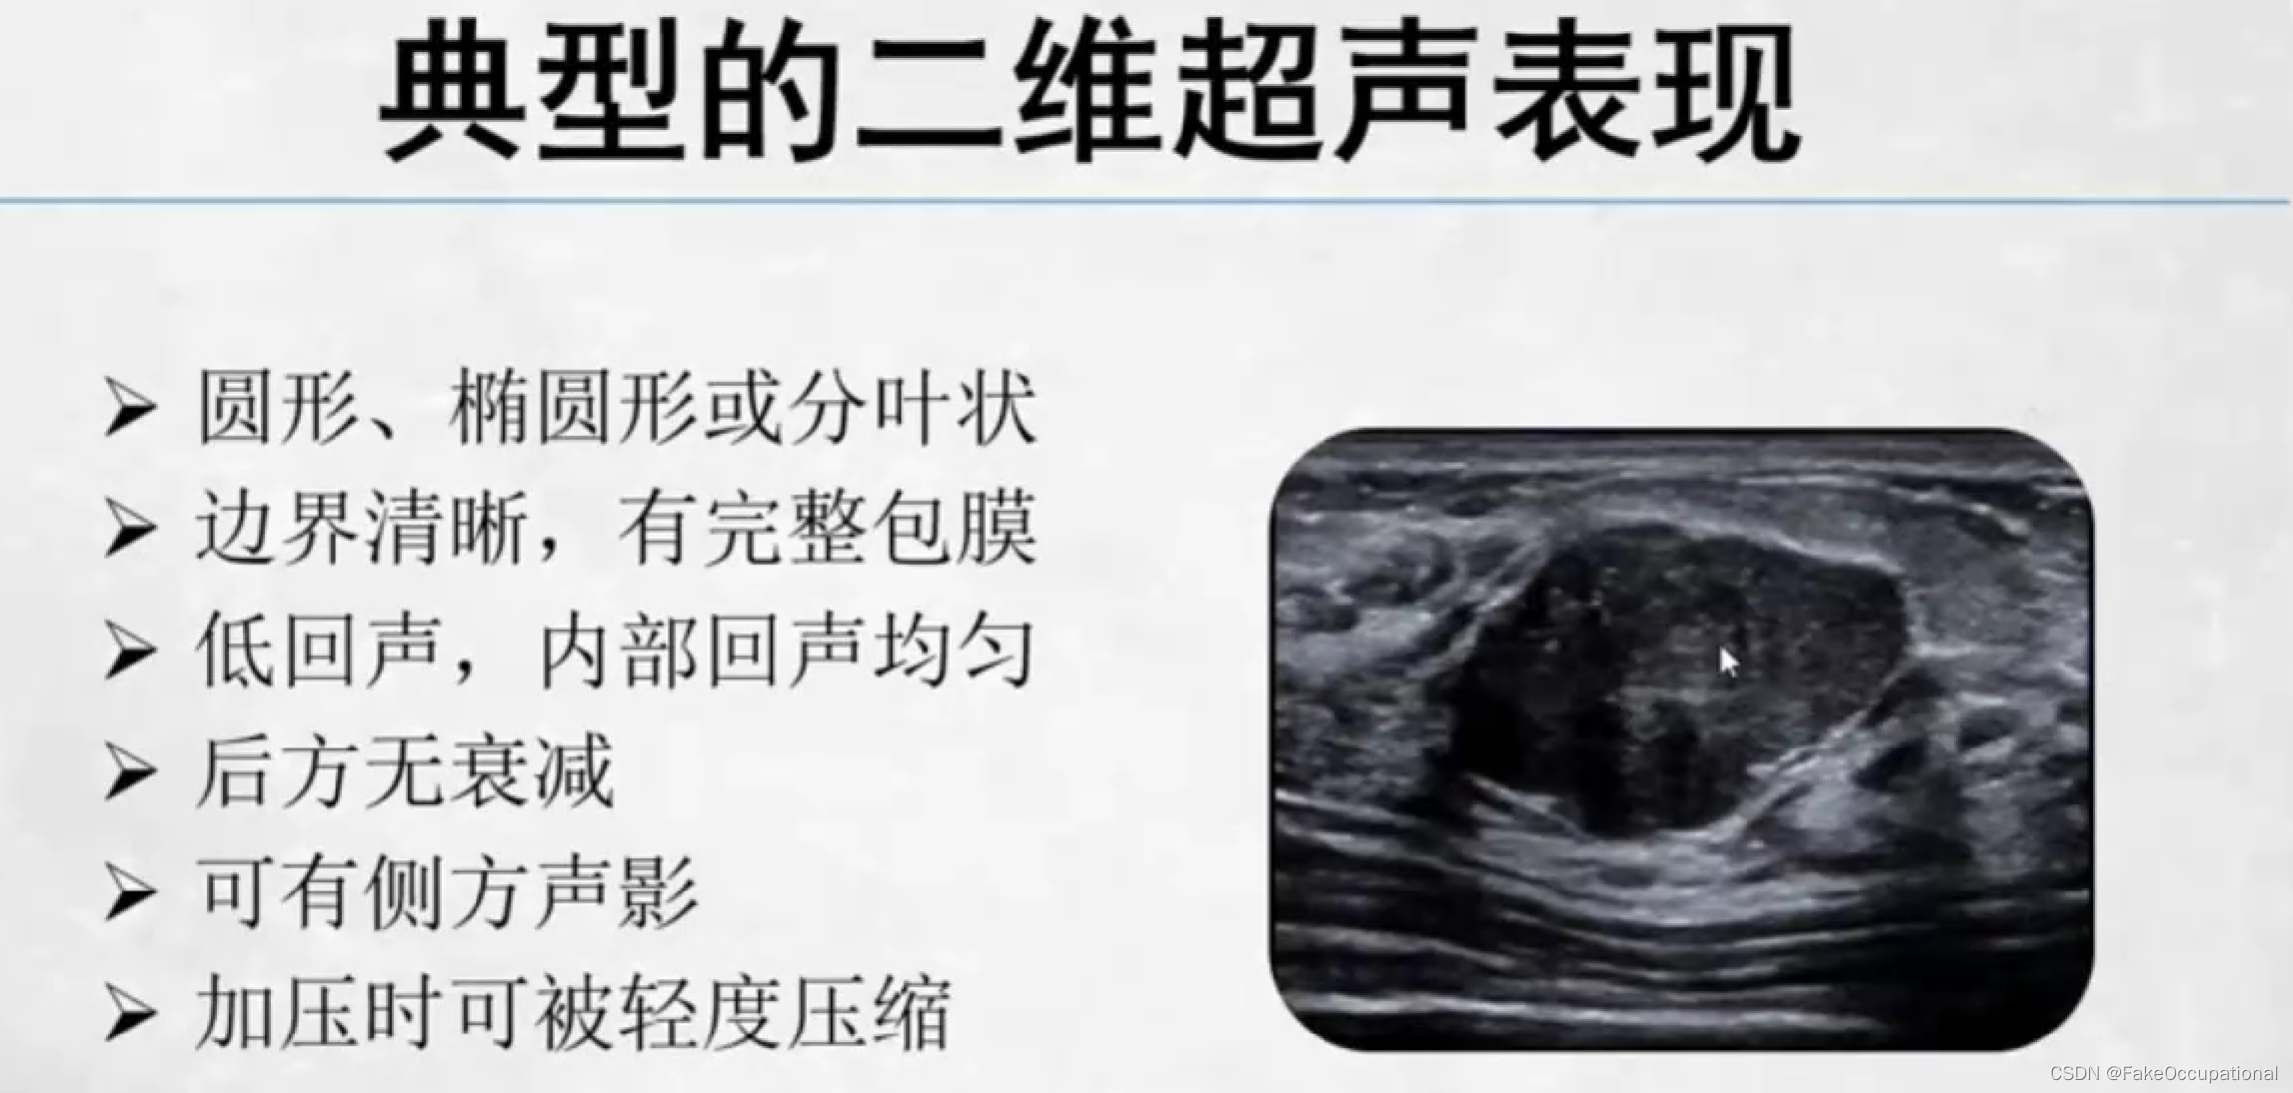

乳腺纤维腺瘤

乳腺纤维瘤 (breast fibroadenoma)

最常见的乳房良性肿瘤,约占乳腺肿瘤的10%

与女性雌激素刺激有关

常见于生育年龄的妇女,特别是30岁以下的女性

无痛、实性、边界清楚、生长缓慢的孤立性结节,触之可移动部分可在同侧或双侧、同时或不同时发生多发性结节